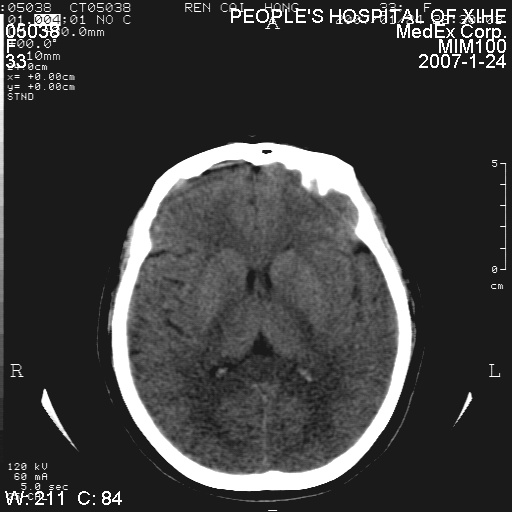

以下是引用卜一在2007-1-25 6:40:00的发言:[br]左侧额叶囊实混杂性病灶,多考虑胶质细胞瘤(ⅱ-ⅲ级),建议增强检查。[br]支持!

以下是引用wwwwtyy在2007-1-25 0:27:00的发言:[br]胶质瘤可能性大,不除外脑白质病变,建议强化

以下是引用xclzq_910在2007-1-25 12:41:00的发言:[br]左额叶条片状低密度灶,考虑占位,建议增强

以下是引用守望可可西里在2007-1-25 0:13:00的发言:[br]左侧额叶囊实混杂性病灶,多考虑胶质细胞瘤(ⅱ-ⅲ级),建议增强检查!